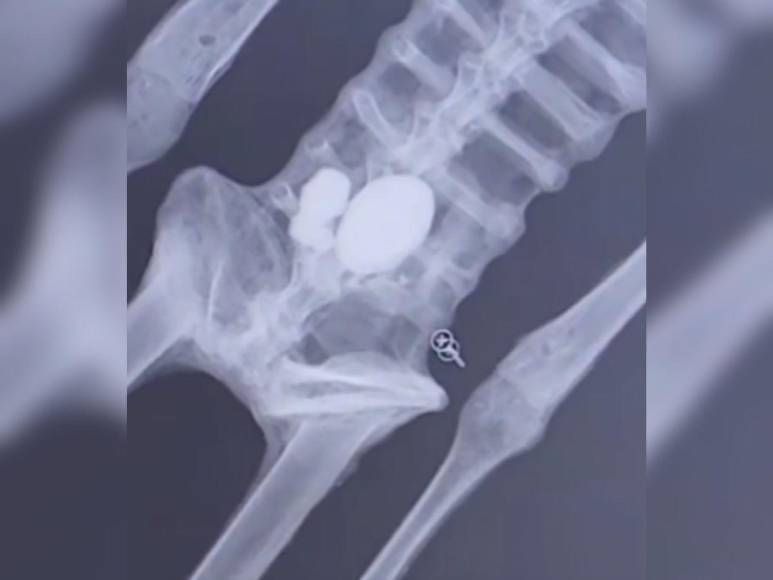

Y quizás uno de los hallazgos más sorprendentes es que en el abdomen se logró evidenciar la presencia de tres huevos. “Que en la cavidad abdominal, gracias a la tomografía, pudimos evidenciar a nivel milimétrico que existen oviductos con la presencia de huevos milimétricos. Esto quiere decir que se encontraban en un proceso de gestación continuo, además de que corrobora al 100 por ciento que son biológicos y orgánicos, ya que el proceso de replicación o reproducción a través de estos huevos y de su desarrollo en el oviducto sería imposible de falsificar”, dijo el encargado del estudio, mientras los presentes guardaban completo silencio y veían las imágenes.

“Algunos de los cuerpos también poseen implantes metálicos que se encuentran perfectamente adosados dentro de la piel y hacia la superficie, haciendo una fusión biofuncional muy impresionante”, indicó, pues se encontraron más restos en esa misma área.

“Estos implantes están hechos con la unión de varios metales como el adsmio, cadmio, mismos que son ocupados actualmente para la telecomunicación satelital”, dijo en otro hallazgo que llama poderosamente la atención.